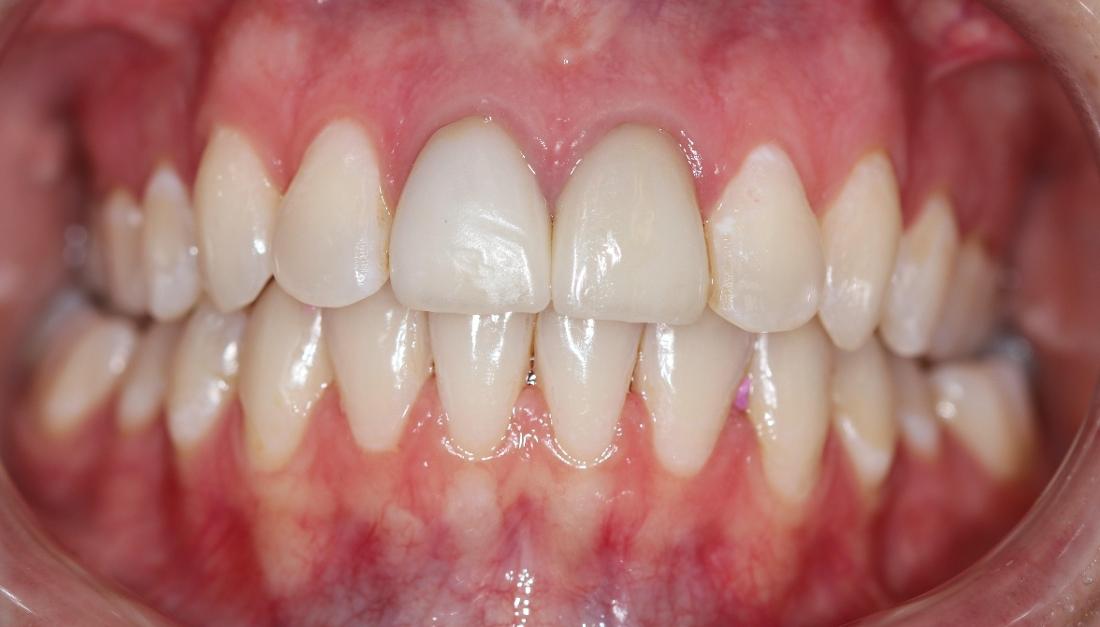

This dental patient arrived at our dental office in Goffstown requesting a straighter smile. We knew this patient would be a perfect candidate for Invisalign clear aligner treatment. After a short consultation, our expert dental team got to work on the Invisalign process and in a few short months, this patient was able to smile with confidence.

One of the first priorities was getting my teeth straightened. I was surprised when I was offered a solution right there at my primary dentist office and did not have to travel to a specialist. I recently got my brackets removed after about a year and the results are AMAZING! The best part was the level of care I received along the way. Any time I had a question or concern it was addressed immediately and they always made time for me to stop by. They have been exceptional with the level of patient care they provide!